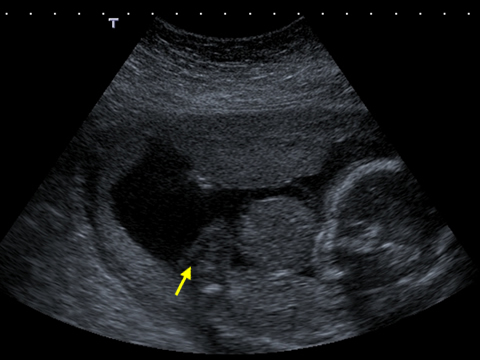

An abdominal wall defect is an abnormal type of hernia either through the cord insertion or by the side of the cord. In this ultrasound image, note the outline of the herniated contents outside the abdomen. The fetal spine and fetal stomach can also be seen.

A long axis scan through the fetus shows the herniated liver coming from the anterior abdominal wall of the fetus. The fetal limbs, abdomen and head can also be seen.